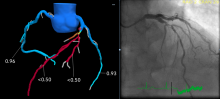

One of the big trends in cardiac computed tomography (CT) imaging has been the introduction of noninvasive fractional flow reserve CT (FFR-CT), which can be used instead of a catheter-based FFR in the cath lab. FFR-CT is being claimed by both cardiology and radiology. The critically important question, however, transcends turf issues. Will patients suspected of having coronary artery disease benefit from its use?